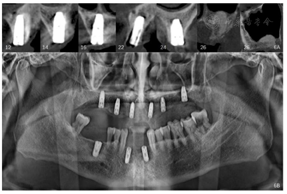

①阿替卡因肾上腺素注射液局麻下拔除13、16,制作上颌过渡性总义齿。②治疗方案设计:拟在12、14、16、22、24、26植入6颗种植体(图4),术前制作种植导板。③13、16牙槽窝愈合6周后,行种植一期手术:16-26牙槽嵴顶全层翻瓣,导板定位定点,16、14分别植入Nobel PCC 4.3 mm×11.5 mm种植体,12、22分别植入Nobel PCC 3.75 mm×11.5 mm种植体,24植入Nobel PCC 4.3 mm×10 mm种植体,26上颌窦外提升植骨,6个月后行种植一期手术,植入Nobel PCC 4.3 mm×10 mm种植体(图5、图6)。④种植二期手术:12、22放置NP30°3.5 mm复合基台;14、24放置RP30°3.5 mm复合基台;16、26放置RP17°3.5 mm复合基台(图7),复合基台均加力至15Ncm。⑤制取种植印模:去除12、14、16、22、24、26复合基台保护帽,放置开口式印模柱,结扎丝连接,3M冠桥树脂固定,制取开口式硅橡胶印模,灌注模型(图8、图9)。

12、14、16、22、24种植一期术后12个月、26种植一期术后6个月,佩戴种植体支持式全牙列固定义齿,义齿戴入后患者唇颊侧丰满度良好,发音清晰,双侧咬合关系恢复良好。曲面体层片示种植体周围骨结合良好(图10)。